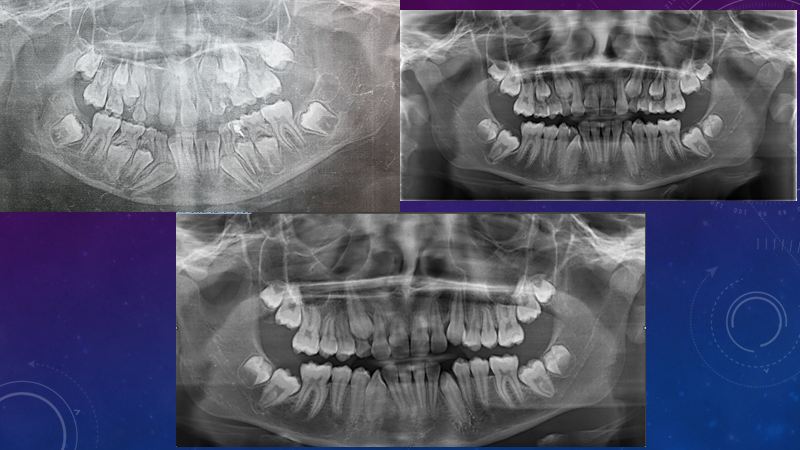

1. Панорамный рентгеновский снимок зубов и челюстей или, как он ещё повсеместно (не совсем правильно) называется - ОПТГ (ортопантомограмма)

Панорамный снимок позволяет изучить наличие

или отсутствие зубов в различные возрастные периоды, а если их делать через определённые промежутки времени, то можно добиться значительного улучшения ситуации без ортодонтических аппаратов.

Благодаря своевременному последовательному удалению временных зубов удалось избежать нарушений прикуса.